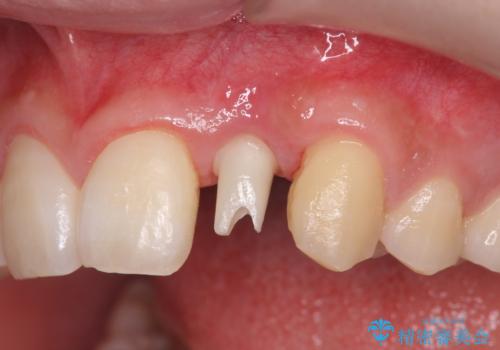

前歯部 インプラント治療

- 前歯の永久歯が元々なく、乳歯を失ったタイミングで前歯の審美性の回復を求めて来院されました。

機能・審美性の回復手段として、インプラント治療・ブリッジ・部分床義歯が考えられます。

それぞれの治療に特徴がありますが、取り外しの必要がなく隣の歯を削る必要も必要ないインプラント治療を選択されました。

前歯部にインプラントを埋入し、きれいに仕上げるためには骨の造成技術や歯肉の厚みを増すような処置を行い、インプラント周囲の環境を整備することが肝要です。